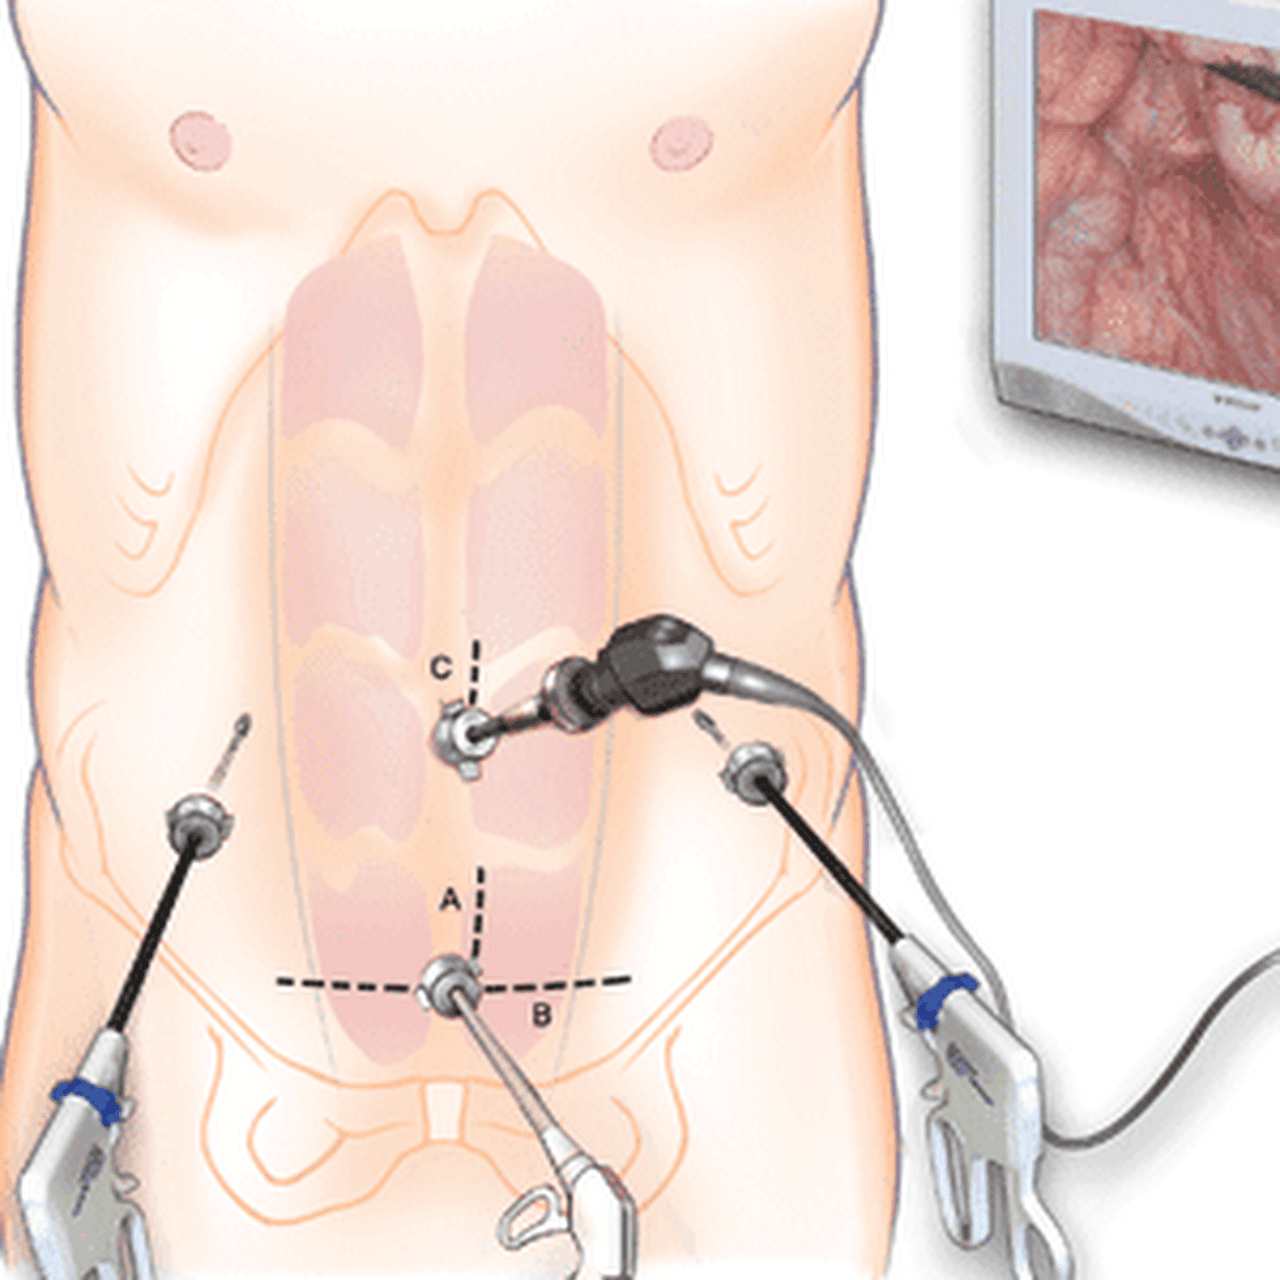

Современные методы лапаротомии и миомэктомии